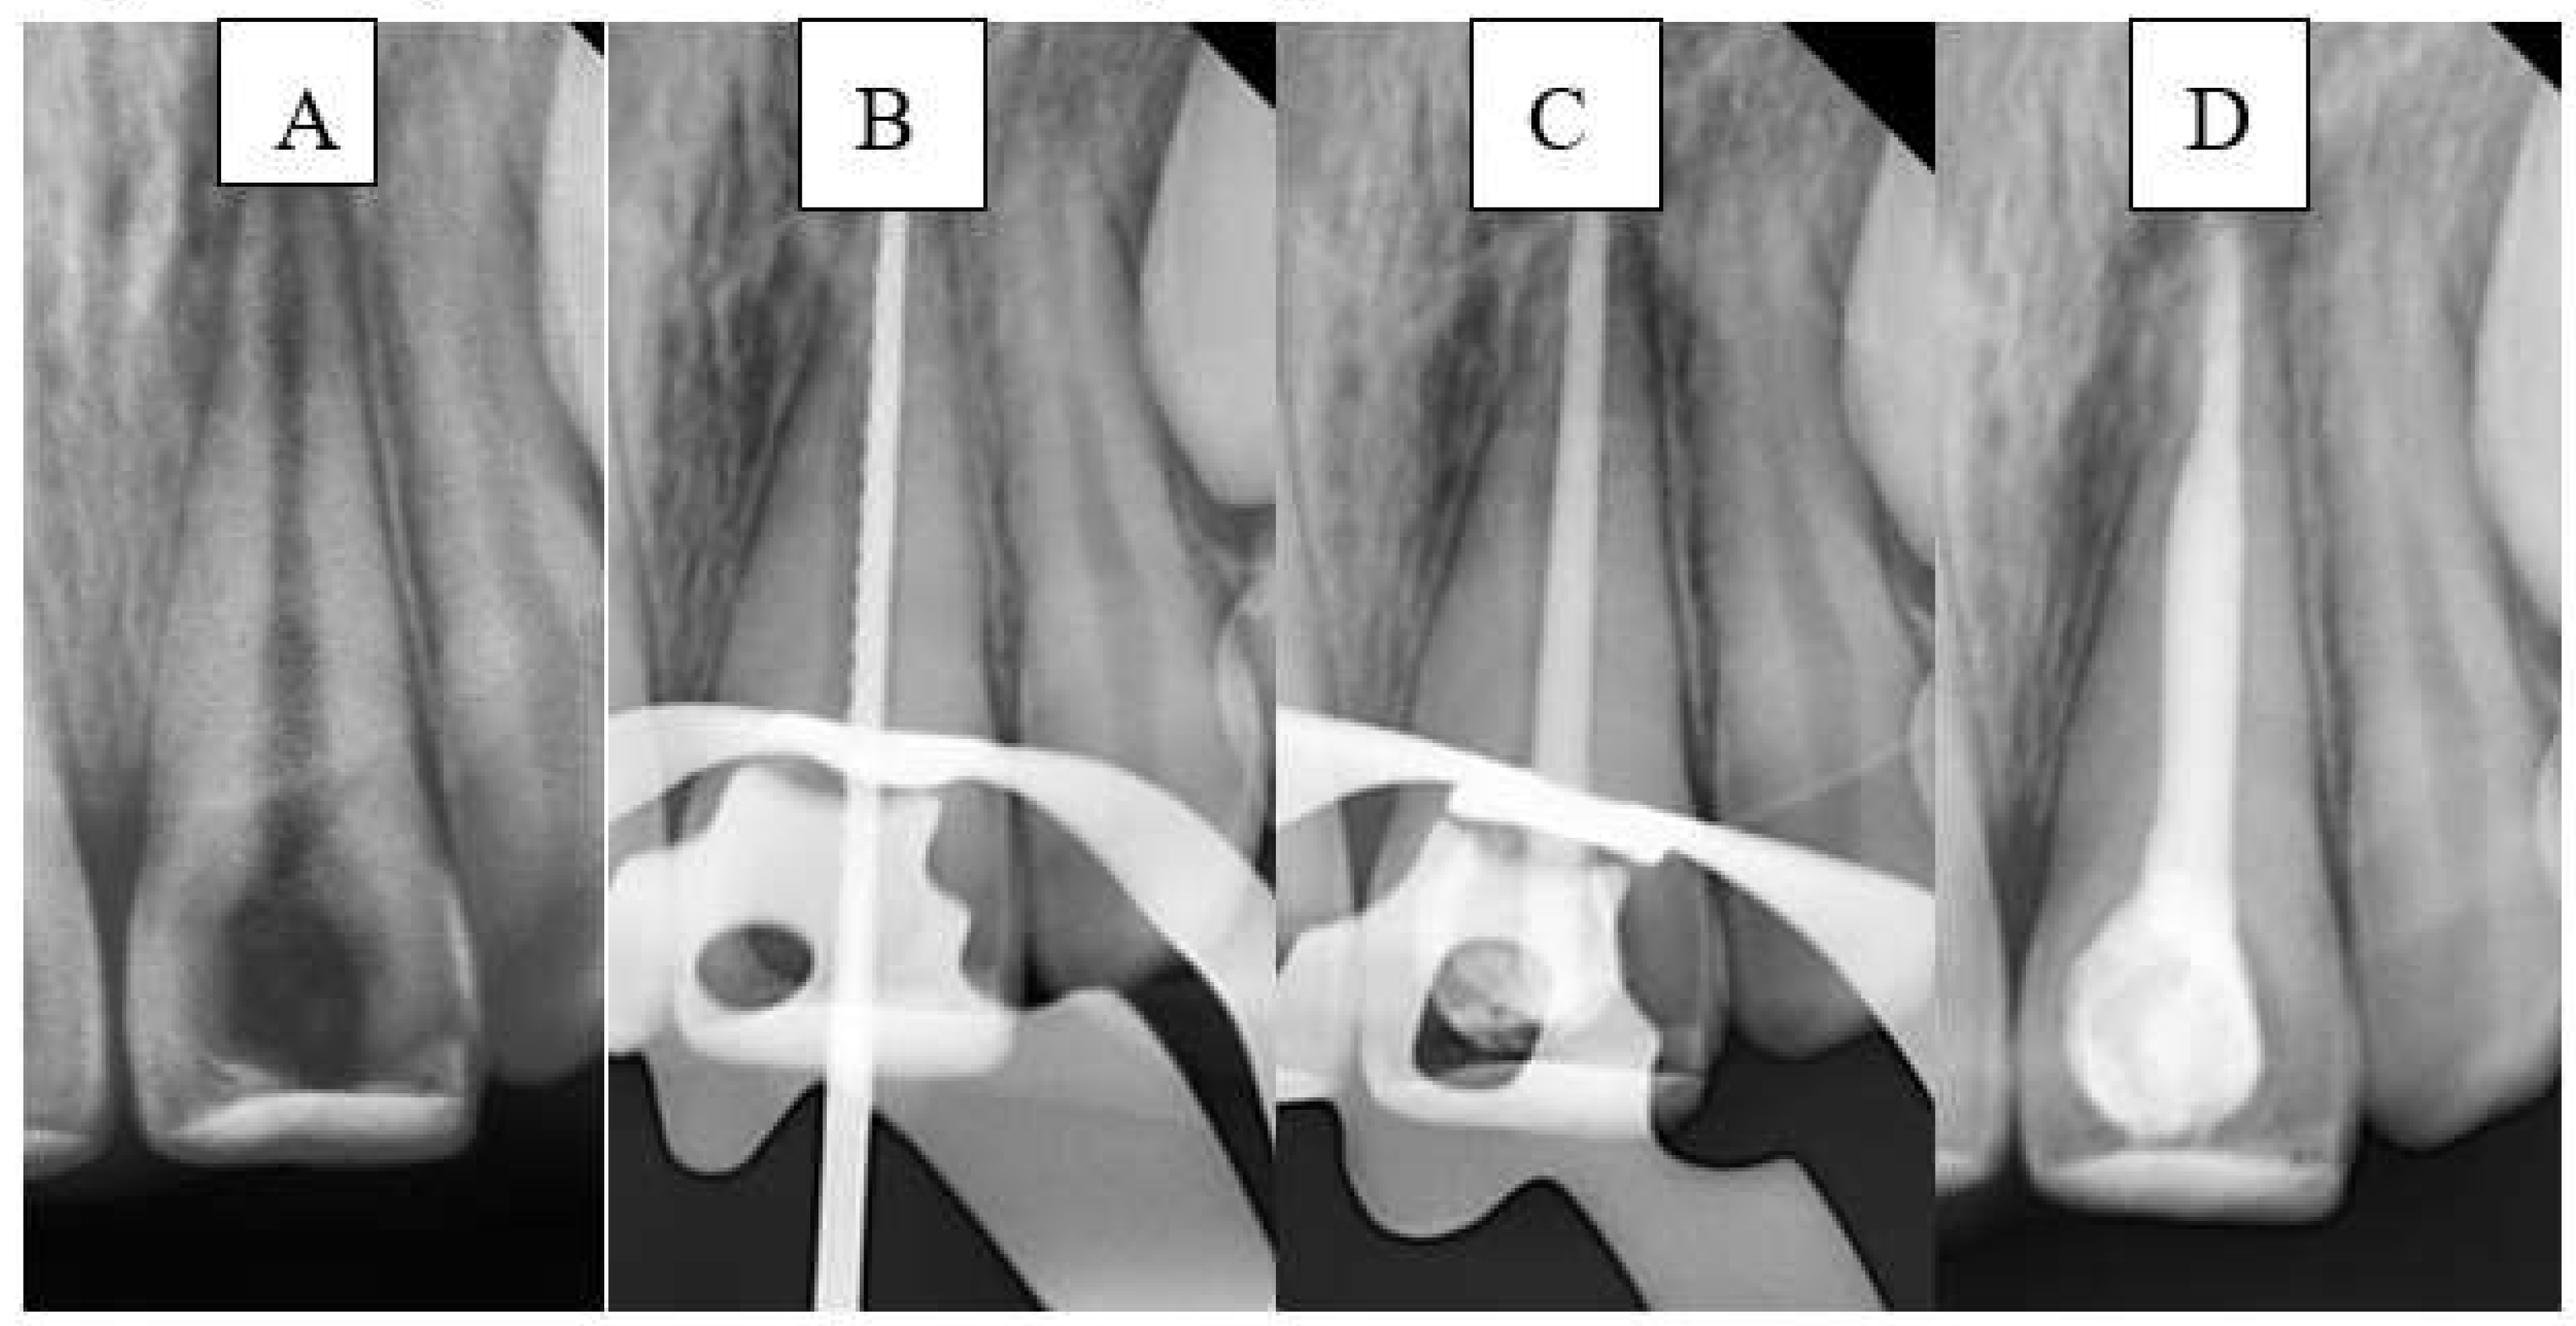

A large-sized (#80, taper of 2%) gutta-percha cone (GC) was inserted. The GC was trimmed to fit the canal width as closely as possible without exceeding the WL. The GC was ensured to make tag-back with the apical third of the immature canal and confirmed with a periapical radiograph. Afterward, it was removed, and the immature canal was gently obturated with BS with an adequate amount, and the GC was inserted again, and another apical radiograph was taken to confirm that the canal was properly filled without gaps and voids. Any BE was recorded at this stage in the DPF. Figure 3 illustrates the steps of the procedure in the SBS group.

Figure 3. Sequential steps of the procedure in the SBS group: A- Preoperative periapical radiograph, B- Working length radiograph, C- Cone fit, and D- Postoperative radiograph.